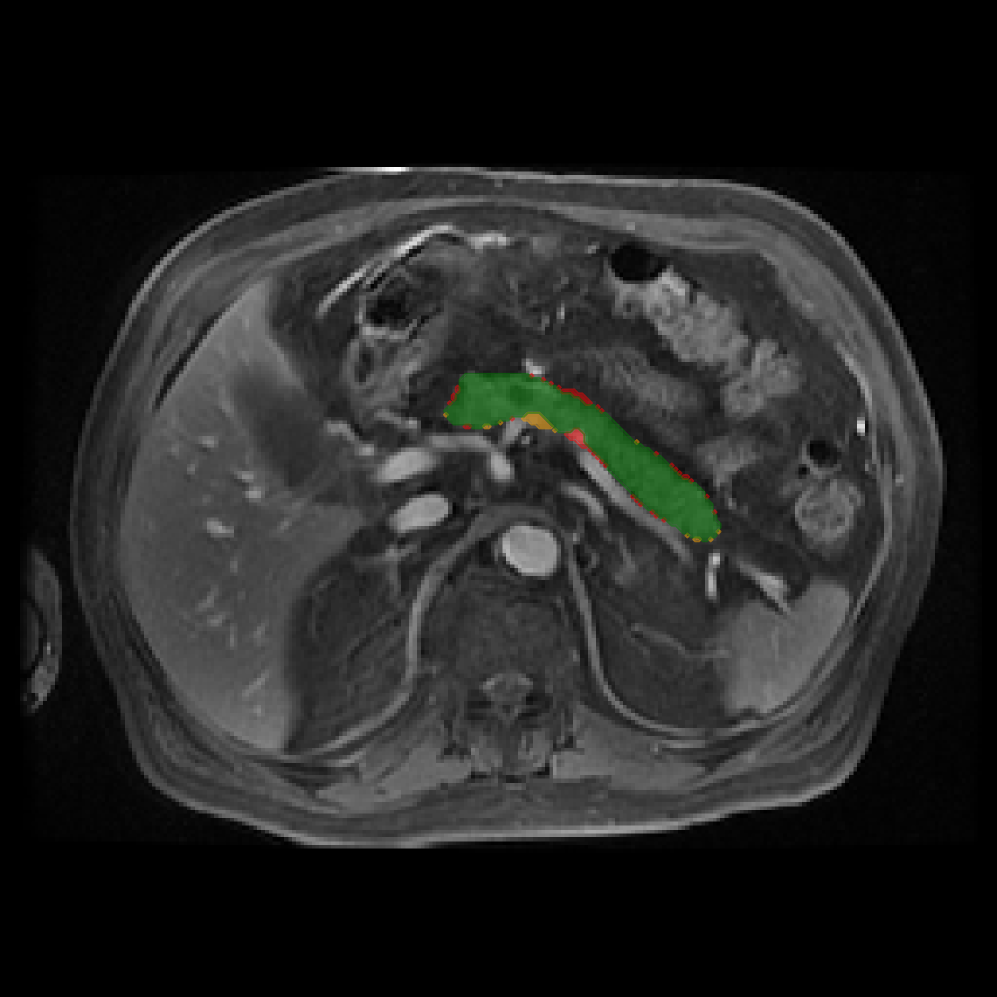

Accurate pancreas segmentation is a critical prerequisite for precise cyst analysis and classification. Recently, we developed PanSegNet [zhang2025large], a novel segmentation architecture incorporating linear self-attention layers [zhang2022dynamic] within the nnUNet framework [isensee2021nnu] to enhance global information modeling capabilities while maintaining computational efficiency (Fig. 1). PanSegNet demonstrated exceptional segmentation performance across both T1W and T2W modalities, achieving mean dice scores of 86.817.30% and 89.626.38%, respectively (Table 1, Fig. 2b-c). This performance significantly exceeded that of Swin-UNETR [hatamizadeh2021swin], one of the most used state-of-the-art transformer-based medical segmentation models, which achieved dice scores of 79.091.40% and 76.290.66% for T1W and T2W, respectively (). In this study, we integrated PanSegNet into our Cyst-X engine along with a classifier for risk prediction. In Section 2.2, we show that the choice of segmentation model affects the classification results. The performance advantage of PanSegNet was consistent across all seven medical centers, demonstrating robust generalization despite variations in imaging protocols and equipment (Table 1). This cross-institutional reliability is particularly important for clinical applications, where model performance must remain consistent regardless of imaging site or acquisition parameters.

We evaluated multiple approaches for IPMN risk classification, comparing radiomics-based methods with deep learning models, and benchmarking against both established clinical guidelines and expert radiologist assessments. Our 3D DenseNet-121 model achieved superior performance in distinguishing high-risk from low-risk and no-risk IPMNs (Table 2). In a direct comparison with the Kyoto Criteria [ohtsuka2024international], our model demonstrated significantly improved diagnostic accuracy (AUC=82.371.02% vs. AUC75%, ) for T2W images. Notably, the performance improvement was most substantial in detecting high-risk lesions (sensitivity 87.8% vs. 64.1%, ), which is clinically critical for preventing missed opportunities for early intervention. To further interpret the model’s feature representation, we performed t-SNE visualization of both the input images and the hidden states from the DenseNet-121. As shown in Fig. 3, input features show limited separation across risk classes, while the learned embeddings exhibit improved clustering by risk category. This indicates that the model successfully learns discriminative representations for IPMN risk stratification.

2.2.1 Importance of accurate pancreas segmentation in classification

To assess the importance of accurate pancreas segmentation in classification, we evaluated how different ROI sources affect DenseNet-121’s performance. Specifically, we compared classification results using ROIs generated by PanSegNet and Swin-UNETR, both under centralized learning, against a baseline using radiologist-defined ROIs. As shown in Table 2, using PanSegNet’s masks resulted in only a modest performance decline, reflecting its strong segmentation quality. In contrast, Swin-UNETR led to a more substantial drop, demonstrating that inferior segmentation can directly compromise classification. For 3-class classification, the mean AUC dropped from 75.59% (radiologist ROI) to 72.26% with PanSegNet, and further to 66.95% with Swin-UNETR on T1-weighted images. On T2-weighted scans, the AUC declined from 81.09% to 74.18% (PanSegNet) and to 69.63% (Swin-UNETR). A similar trend was observed in 2-class classification: on T1W, AUC dropped from 78.13% to 74.84% (PanSegNet) and 70.20% (Swin-UNETR); on T2W, from 82.37% to 77.01% and 68.92%, respectively. These results emphasize that accurate segmentation—particularly via PanSegNet—is not only essential for volume estimation but also critical to preserving downstream classification performance in the Cyst-X pipeline.